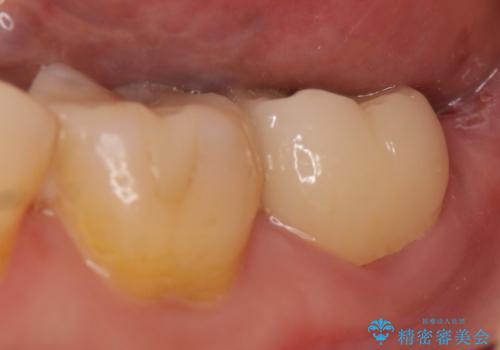

今回用いたオールセラミッククラウンはジルコニアフレームという白い素材の上にセラミックを盛っているため、審美性が非常に高いのが特徴です。

また、ジルコニアは人工ダイヤモンドの材料にも使われているほど高い強度を持っており、そのためオールセラミッククラウンは審美性だけでなく、奥歯やブリッジの補綴も可能とするクラウンです。